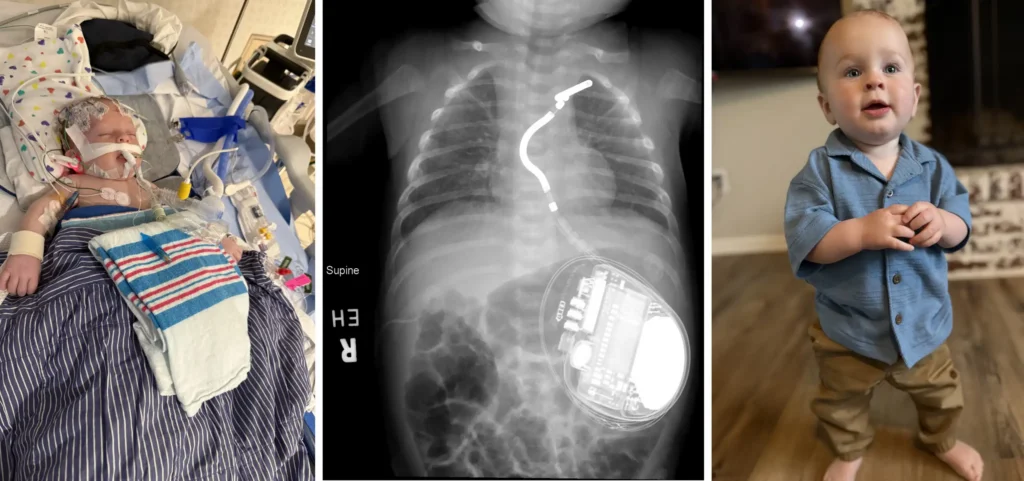

Four Outstanding Research Achievements of 2025